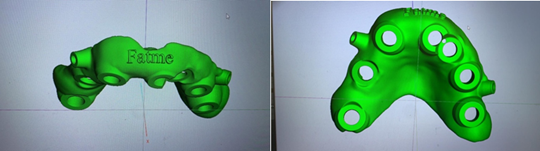

Step 7: Production of the Printed Surgical Guide

Surgical Guide Design

Surgical Guide Fabrication

Assembly and Sterilization

Figure 17: Guide in progress.

Figure 18: Guide ready to print.

Figure 19: Guide printed with the sleeves and fixations pins placed.